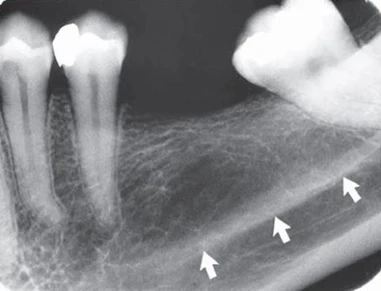

Ống dinh dưỡng chứa một bó thần kinh mạch máu và có hình ảnh dạng đường thấu quang với chiều rộng khá đồng đều. Chúng thường được thấy nhất ở phim quanh chóp ở hàm dưới chạy dọc từ phía dưới ống thần kinh xương ổ răng dưới đến một chóp răng hoặc vào khoảng giữa các răng cửa hàm dưới. Thấy được chúng trong khoảng 5% trường hợp trên tất cả bệnh nhân và thường ở người nam, da đen, người lớn tuổi và những người có huyết áp cao hoặc bệnh lý nha chu tiến triển. Chúng cũng cho thấy gờ xương mỏng, hữu ích khi đánh giá implant. Vì chúng có giải phẫu là khoảng trống bao quanh bởi thành là xương vỏ nên hình ảnh thường cho thấy biên giới xương dày. Đôi khi ống dinh dưỡng vuông góc với xương vỏ cho hình ảnh một vòng tròn thấu quang giống như hình ảnh thấu quang của bệnh lý.